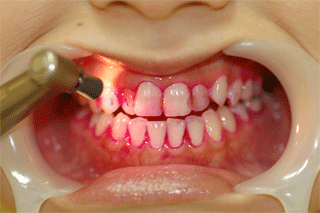

たばこのヤニのついた歯へのPMTCの施術例

PMTC施術前   PMTC施術後

ヤニや歯石がたくさんついています

スケーラーやジェットポリッシャーで汚れを落とします。